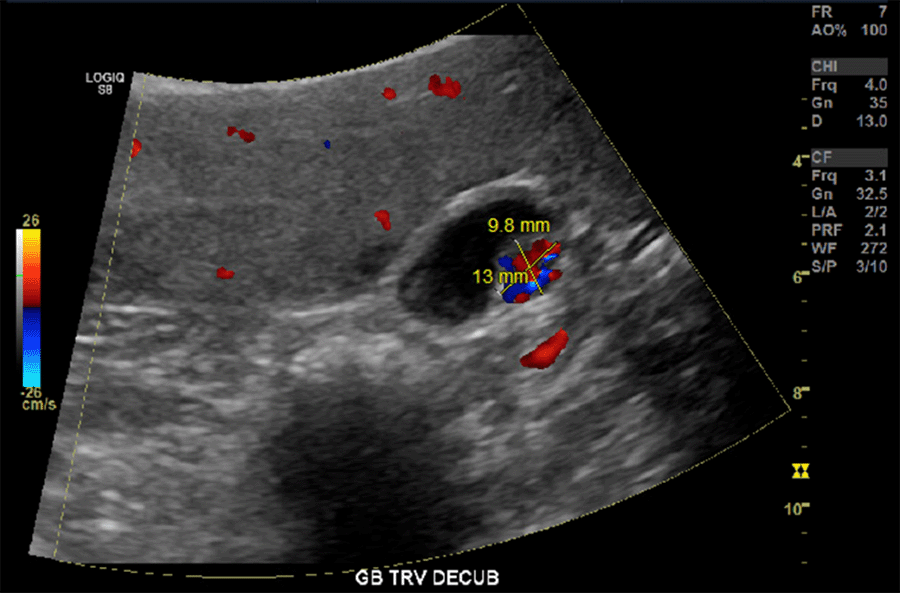

The patient then returned to our emergency department two months later. During the emergency department workup, she had a CAT scan of the abdomen and pelvis that again noted the gallbladder mass along the anterior wall, now measuring 1.2 × 1.6 cm (Figure 2). At that time, she was admitted for MRI/MRCP. The MRI characterized the lesion as a polyp, with bulging of the wall concerning for extraanatomic extension anteromedially, but again was unable to say whether there was an underlying malignancy definitively. The patient was optimized and underwent an uneventful laparoscopic cholecystectomy, finding grossly intact serosa without extension of the lesion into surrounding structures. The decision was made at that time to perform a simple cholecystectomy. The patient recovered without complication from the surgery and was discharged home. The final pathology returned as a 1 × 1 cm paraganglioma with negative margins.

Figure 2. Axial View of Hyper-Vascular Enhancing Gallbladder Mass during CT with IV Contrast. Published with Permission